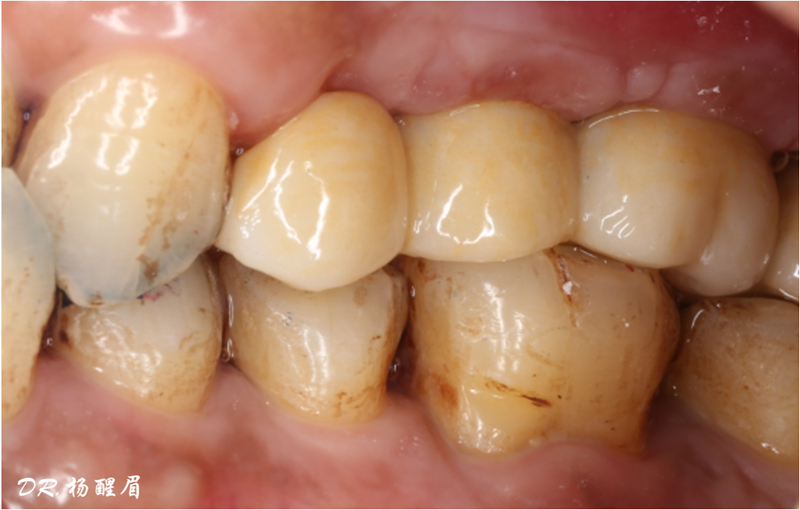

®袖口形態(tài)

®基樁形態(tài)

修復完成

®多顆植體位點及角度的精確性,確保后期修復方案順利完成,也使患者能在使用過程中承受最佳的咬合力